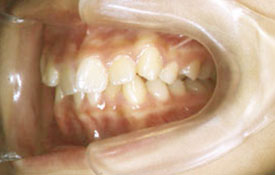

インビザラインの治療例:CASE-2

| プロフィール | 15歳 男性 |

| 所見 | アメリカから転院されて来られた方です。 インビザラインで上下顎の矯正治療を開始し下顎はアメリカで終了しており、上顎のみ治療の後期を担当しました。 アイライナーの装着は、1日平均22時間ほどでした。 |